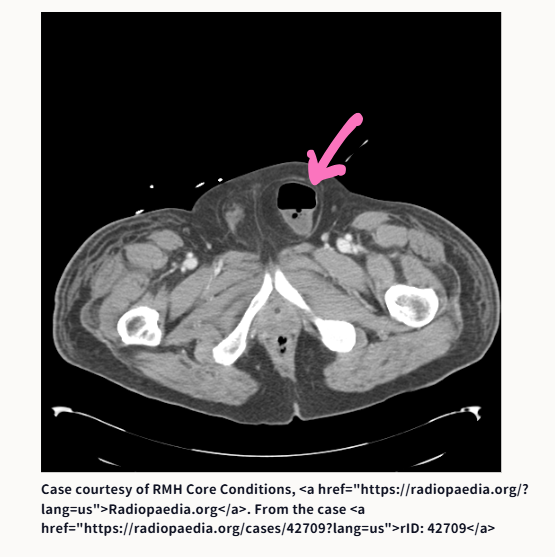

③腸閉塞です。原因は何でしょうか?

③腸閉塞の原因は、鼠径ヘルニア嵌頓です

こあら先生が提示したCT画像は、以下のサイトからのものです。ピンクの矢印は、こあら先生が書き込んだものです。